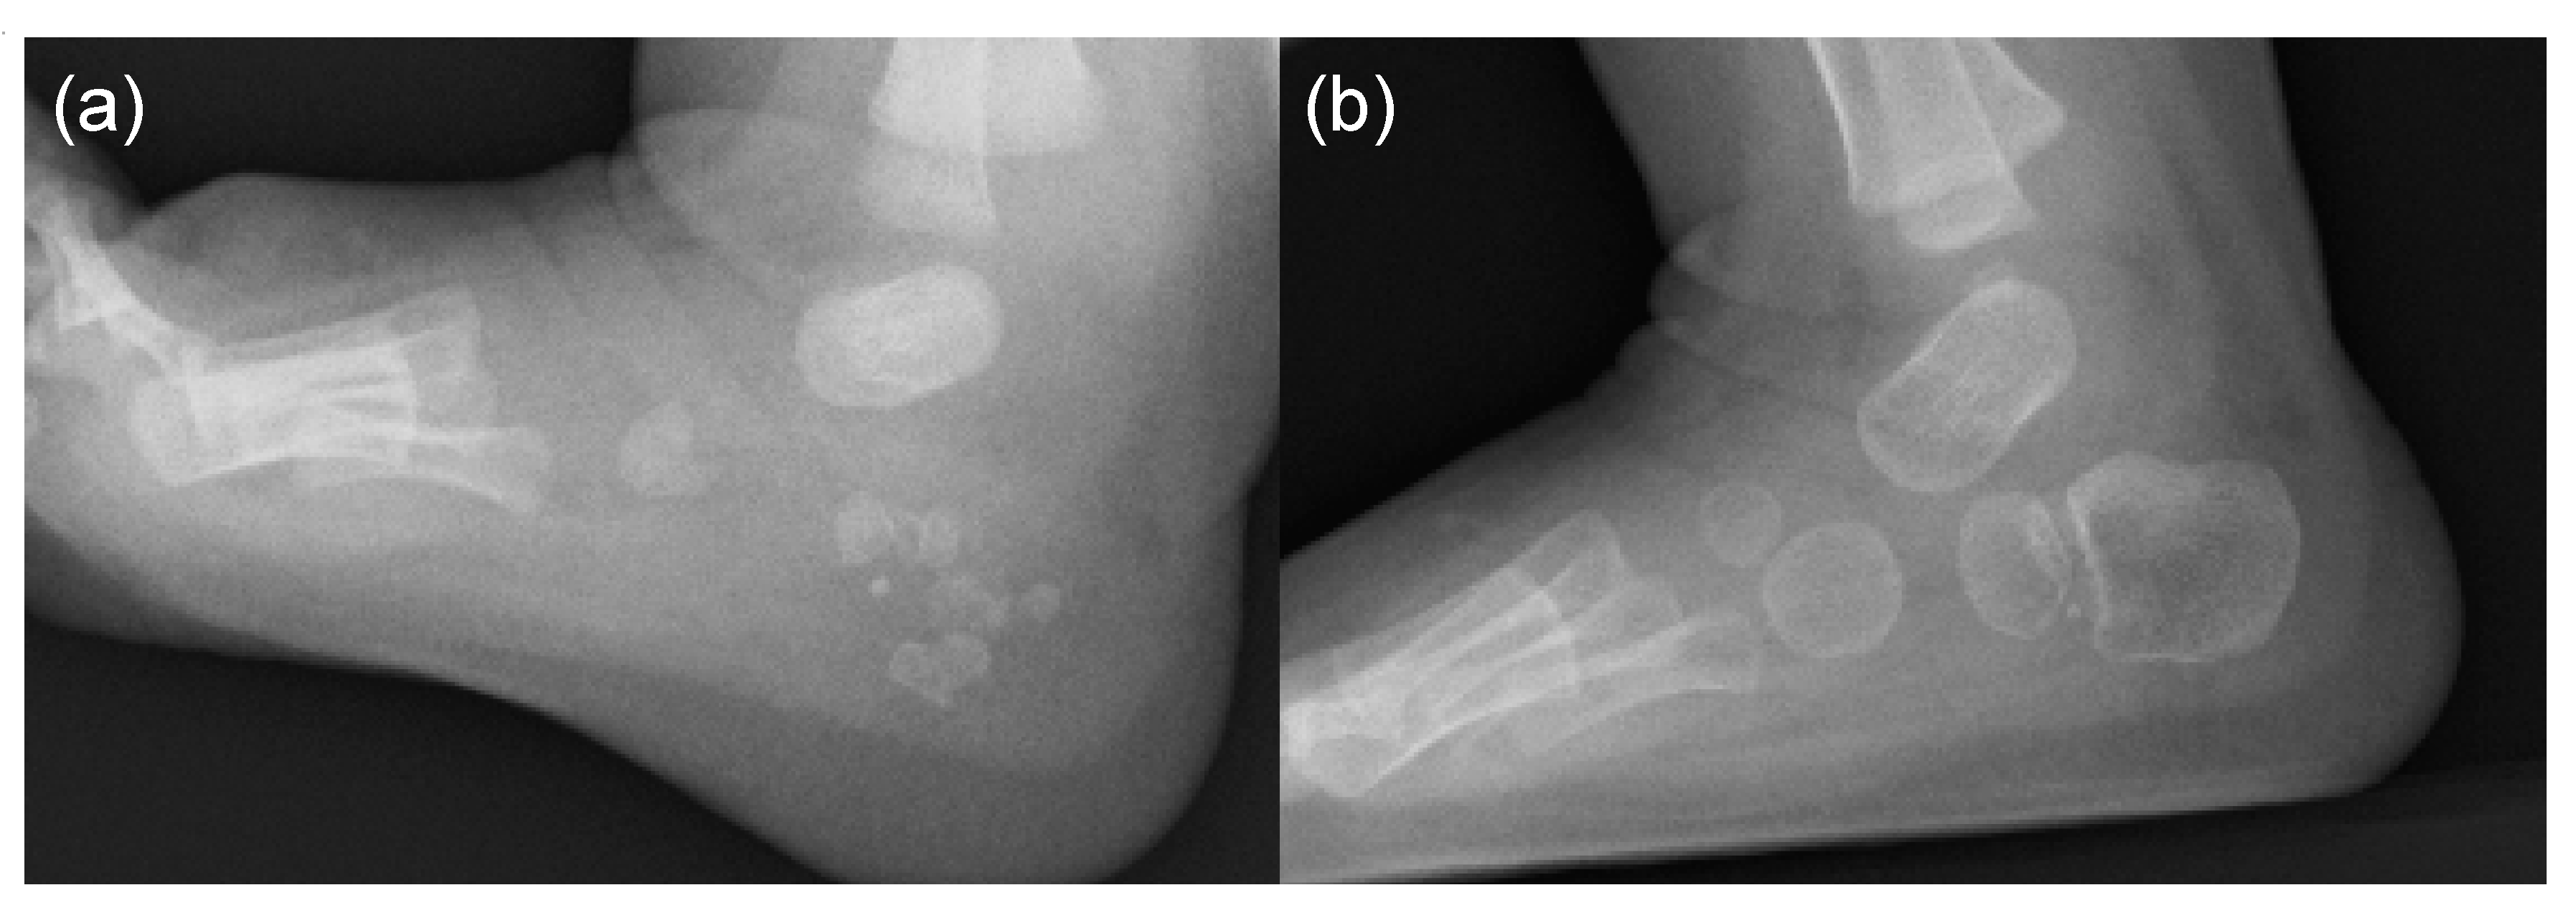

- Hasegawa, S.; Victoria, T.; Kayserili, H.; Zackai, E.; Nishimura, G.; Haga, N.; Nakashima, Y.; Miyazaki, O.; Kitoh, H. Characteristic calcaneal ossification: An additional early radiographic finding in infants with fibrodysplasia ossificans progressiva. Pediatr. Radiol. 2016, 46, 1568–1572. [Google Scholar] [CrossRef] [PubMed]